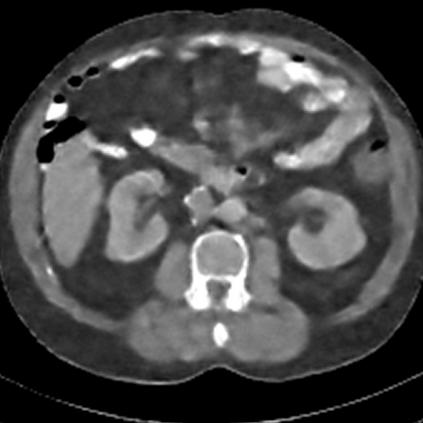

Sparse-view computed tomography (CT) -- using a small number of projections for tomographic reconstruction -- enables much lower radiation dose to patients and accelerated data acquisition. The reconstructed images, however, suffer from strong artifacts, greatly limiting their diagnostic value. Current trends for sparse-view CT turn to the raw data for better information recovery. The resultant dual-domain methods, nonetheless, suffer from secondary artifacts, especially in ultra-sparse view scenarios, and their generalization to other scanners/protocols is greatly limited. A crucial question arises: have the image post-processing methods reached the limit? Our answer is not yet. In this paper, we stick to image post-processing methods due to great flexibility and propose global representation (GloRe) distillation framework for sparse-view CT, termed GloReDi. First, we propose to learn GloRe with Fourier convolution, so each element in GloRe has an image-wide receptive field. Second, unlike methods that only use the full-view images for supervision, we propose to distill GloRe from intermediate-view reconstructed images that are readily available but not explored in previous literature. The success of GloRe distillation is attributed to two key components: representation directional distillation to align the GloRe directions, and band-pass-specific contrastive distillation to gain clinically important details. Extensive experiments demonstrate the superiority of the proposed GloReDi over the state-of-the-art methods, including dual-domain ones. The source code is available at https://github.com/longzilicart/GloReDi.